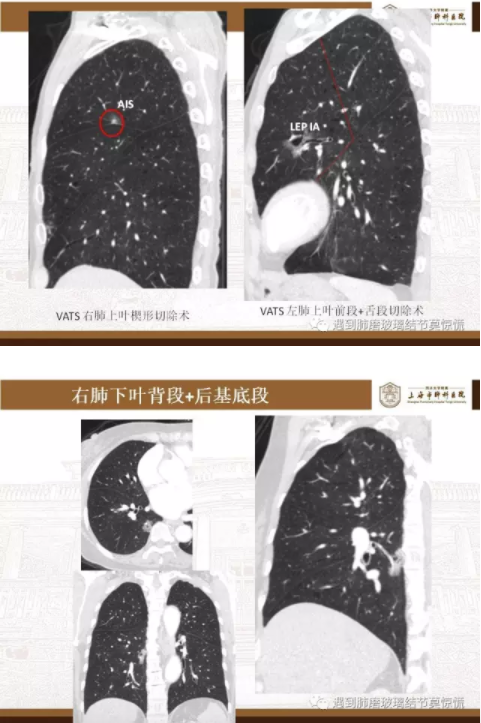

元芳,表现为肺磨玻璃结节的早期肺癌,特别是病灶位置较深者,可以采用肺段切除,以减少肺功能损失,同时保证肿瘤根除。

元芳,你看下图,肺段切除包括:姑息性肺段切除与意向性肺段切除。

下面就我们的病例分析一下怎么进行肺段切除。

MIA= 微浸润腺癌   IA= 浸润性腺癌   AIS= 原位腺癌   AAH= 不典型腺瘤样增生